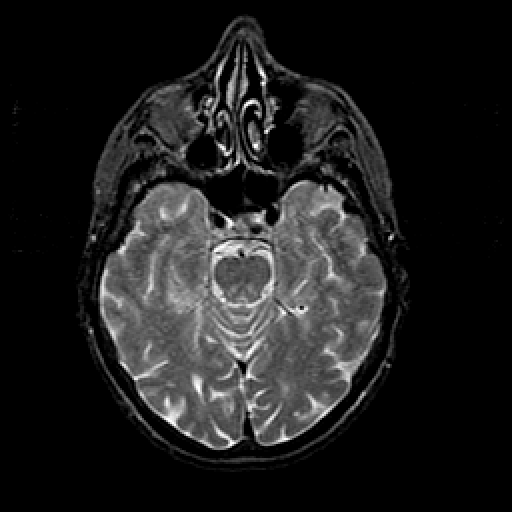

T2-weighted structural MR: Slice 19

Slice 19